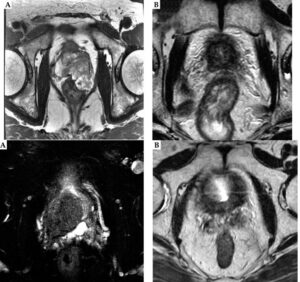

繰り返しになりますが、岡本メソッドによる小線源治療を行うことにより骨転移や臓器転移さえなければ上述のような難治症例や骨盤内リンパ節転移を認める症例であっても、ホルモン治療の期間は小線源終了後から6か月と短い治療で完治させることが出来るのが特徴です。また前立腺癌の中には導管癌と呼ばれる悪性度が高くまた再発率および死亡率の極めて高い前立腺癌が存在します。いわゆる難治性前立腺癌に分類されるものです。私は局所進行をきたした超高リスク導管癌 (T3b症例)についても同様のメソッドを用いることにより、長期間の経過観察を経ても完全に根治できていることを国際雑誌に公表しました:(Journal of contemporary brachytherapy 2022)。Very high-risk locally advanced prostate ductal adenocarcinoma cured using low-dose-rate brachytherapy, with seminal vesicle implantation in combination with external beam radiotherapy at a biologically effective dose ≥ 220 Gy: two case reports with a long-term follow-up – PMC

The Upper Image: Axial T2-weighted magnetic resonance images of the prostate of case 1. A) Locally advanced prostate ductal adenocarcinoma (PDA) before the treatment. Note that a large prostate tumor extends into the rectal wall (T3b); B) The shrinkage of the tumor observed at 11 years after the treatment. The Lower image: Axial T2-weighted magnetic resonance images of the prostate of case 2. A) Locally advanced prostate ductal adenocarcinoma (PDA) before the treatment. Note that a large prostate tumor extends into the right seminal vesicle (T3b); B) The shrinkage of the tumor observed at 8 years after the treatment.

At their latest follow-up evaluations (case 1 at 11.5 years after completion of EBRT, and case 2 at 8 years after completion of EBRT), PSA values in both the patients were 0.01 ng/ml (Table 3). Serum testosterone values of both the patients were within normal range (Table 3), indicating that the effect of ADT on the above-mentioned low PSA level was negligible.